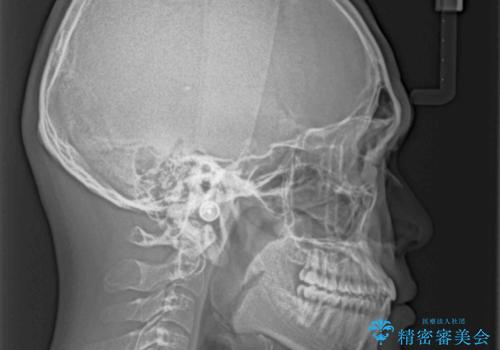

骨格的に下顎が前方に位置していましたが、歯列矯正で改善できると判断し、ワイヤー装置にて矯正治療を行うこととしました。

骨格的な左右差も顕著であったため、正中は合わず、上下前歯の一部が接触しない咬み合わせとなることが予想されましたが、正中はもともとのズレが小さかったことから、合わせることができました。